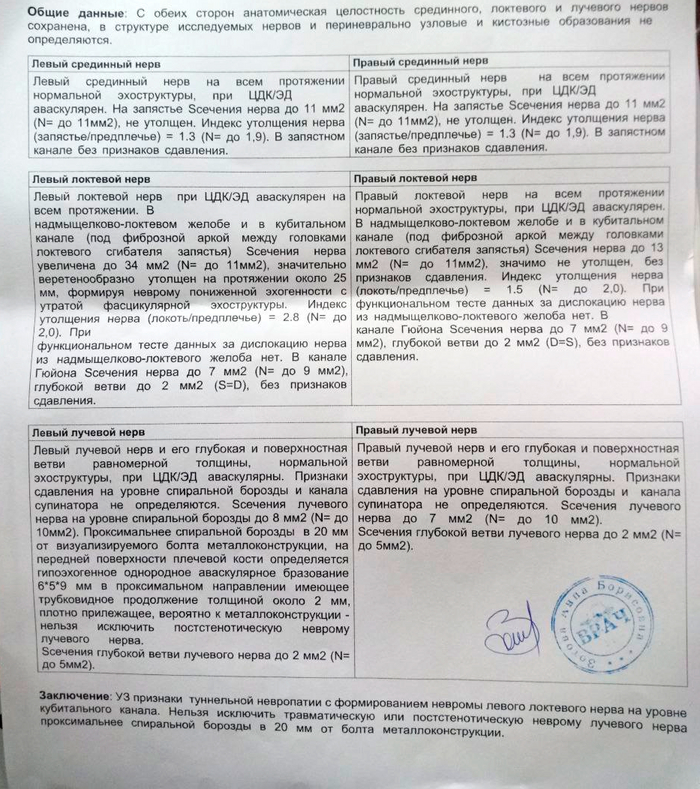

Врач-нейрохирург, специализирующийся на подобных случаях, пересмотрел полученные изыскания и проверил работоспособность конечности. Вердикт был суров - ситуация тяжёлая, но поправимая. Вся рука функционирует отлично, даже с учётом двух месяцев в повязке. Сустав в плече работает плохо, потому что разрабатывать его не даёт боль, но лучше починить старое, чем потом привинчивать новое. Пилюльки для снятия нейропатической боли прописаны правильные, но дозировку нужно больше раза в два. Плюс добавить антидепрессанты, которые так же работают со снятием боли, пусть даже будут жёсткие побочные эффекты. И быстренько разрабатывать руку, как только боль немного спадёт. Разработаю руку - победю. Пожалею себя - будут плохие последствия.

Диагноз невропатолога Комплексный регионарный болевой синдром подтверждён. Руку не отрезаем, нервы не трогаем, посттравматическая нейропатия лучевого нерва под вопросом.